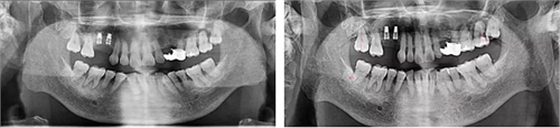

術(shù)后8個月 術(shù)后10個月

術(shù)后13個月

術(shù)后14個月